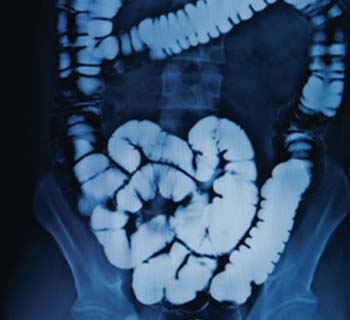

Early symptoms of coeliac disease and IBS can be difficult to identity. Dawn Gay explains how pharmacy teams can spot the warning signs

Wind, constipation, indigestion and diarrhoea are common OTC complaints. The truth is in the figures €“ the gastrointestinal market is worth a huge £258 million. But gut disorders are not so clear-cut. Complex conditions like coeliac disease, irritable bowel syndrome and inflammatory bowel diseases, from colitis to Crohn's, present blurred lines for pharmacists who must identify symptoms and impart lifestyle advice.